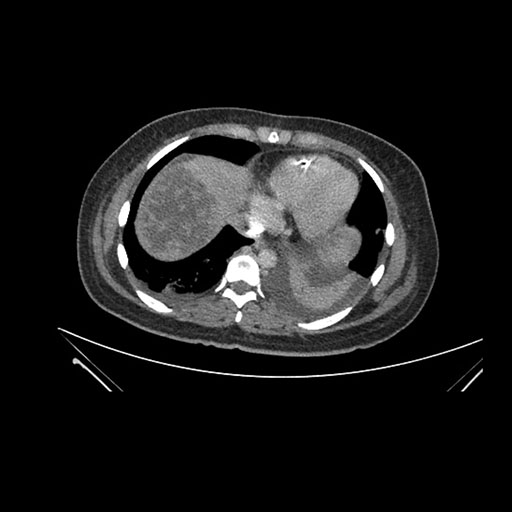

Imaging Analysis

Look through the patient's CT scan to identify any areas of concern for the necessary procedure.

Axial Venous